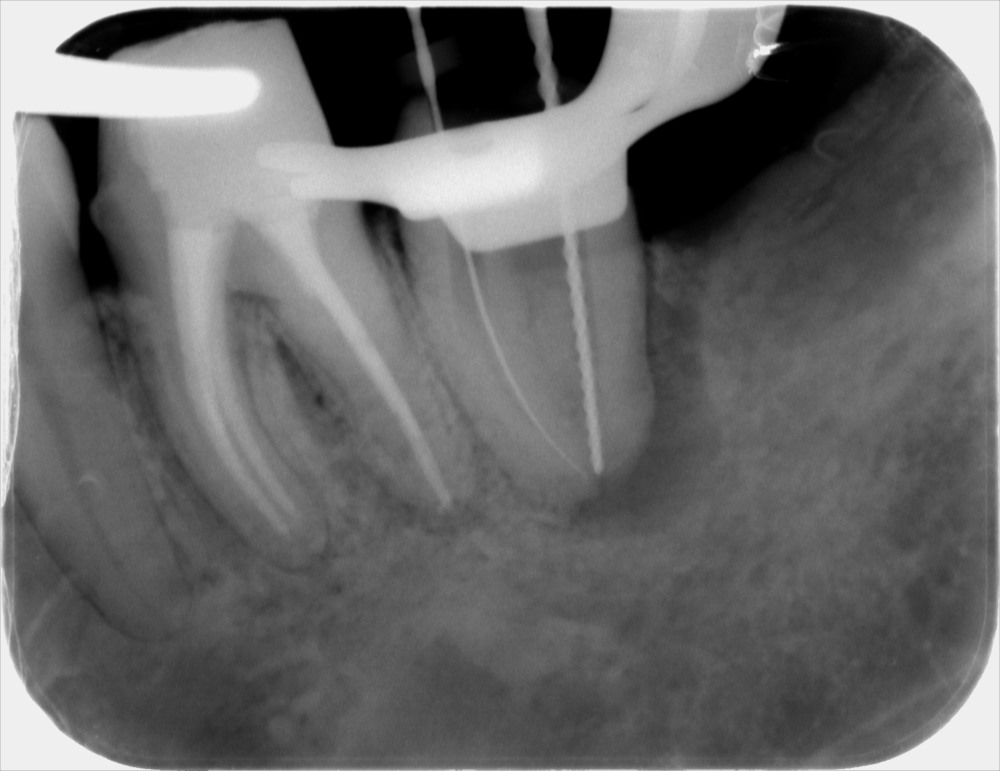

術前のレントゲン写真です。根の先に黒い像があります。根の内部に汚れがある証拠です。

根の内部の感染を取り除いたあと、根の長さを測っているレントゲン写真です。